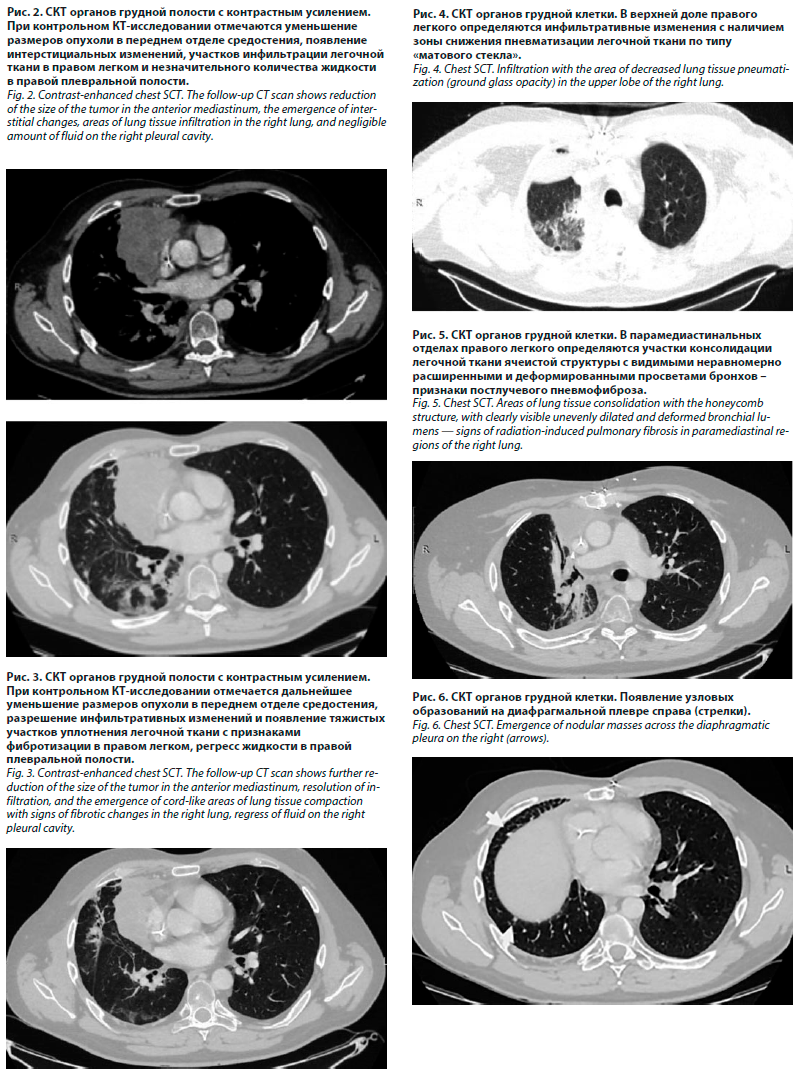

Пациент К., 42 лет, обратился к радиологу отделения лечения лучевых повреждений МРНЦ в мае 2023 г. с жалобами на одышку при умеренной нагрузке, боли в грудной клетке, надсадный кашель с небольшим количеством слизисто-гнойной мокроты, повышение температуры тела до субфебрильных значений. В анамнезе – тимома, тип В3, ycT4N0M1a, IV стадия, с инвазией в перикард, инфильтрацией клетчатки средостения, верхней полой вены, правого предсердия, правой легочной артерии, верхней легочной вены, верхней и средней долей легкого, междолевой плевры, лимфатических узлов корня легкого, диссеминацией по плевре (рис. 1).

Пациент К., 42 лет, обратился к радиологу отделения лечения лучевых повреждений МРНЦ в мае 2023 г. с жалобами на одышку при умеренной нагрузке, боли в грудной клетке, надсадный кашель с небольшим количеством слизисто-гнойной мокроты, повышение температуры тела до субфебрильных значений. В анамнезе – тимома, тип В3, ycT4N0M1a, IV стадия, с инвазией в перикард, инфильтрацией клетчатки средостения, верхней полой вены, правого предсердия, правой легочной артерии, верхней легочной вены, верхней и средней долей легкого, междолевой плевры, лимфатических узлов корня легкого, диссеминацией по плевре (рис. 1).В марте 2022 г. проведено 4 цикла неоадъювантной ХТ по схеме САР с положительной динамикой, торакотомия с биопсией плевры, процесс признан нерезектабельным. В августе – ноябре 2022 г. пациент получил